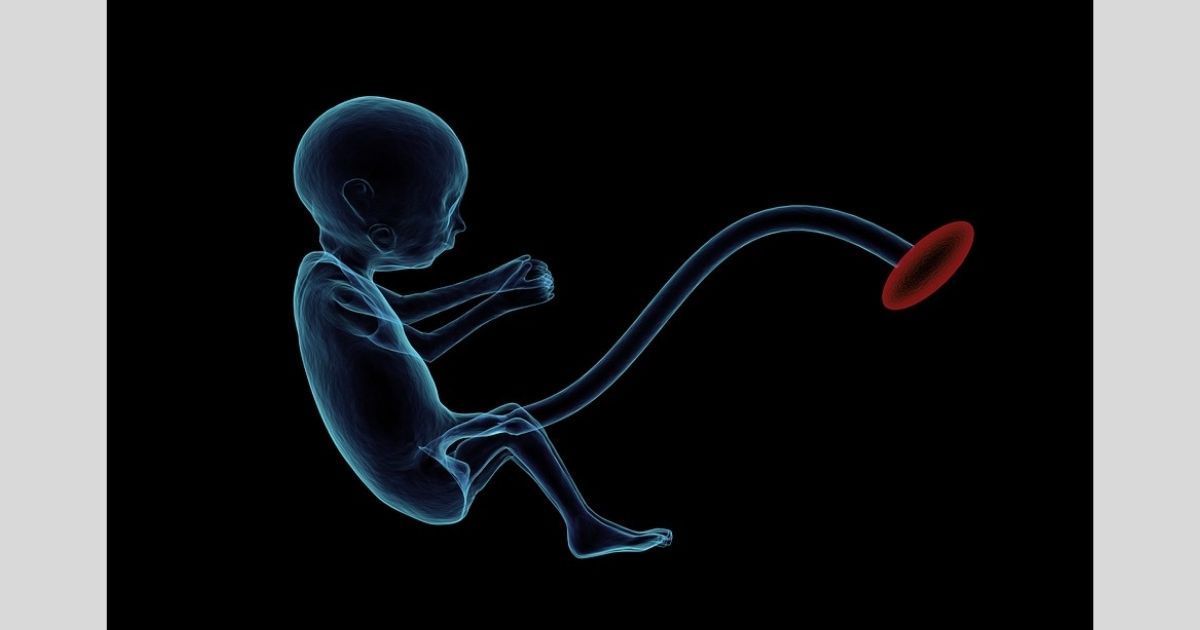

Weeks after @sueomanii gave birth, she experienced severe abdominal pain and was rushed to the hospital. This is when she found out that she still had some of her placenta left inside her womb.

Apparently, @sueomanii was left with a retained placenta that is the size of her hand inside her, which required surgery to remove it.

She then explained that she had retained a placenta.

When a part of the placenta remained in the womb after giving birth and, if not treated, it can cause serious complications to the mother.

“Turns out the midwife didn’t clean me properly and there was retained placenta inside me that was the size of my hand,” she said. “I later had a scan to see if there was any more.”

“The scan showed that there was in fact more retained placenta which I then needed surgery to get rid of the remaining,” she added. “The retained placenta smelt so bad which could’ve led to an infection.”

“Complications of a retained placenta include heavy bleeding, infection, uterine scarring, blood transfusion, and hysterectomy,” @sueomanii explained. “Any of these complications can lead to death if not diagnosed and treated quickly.”